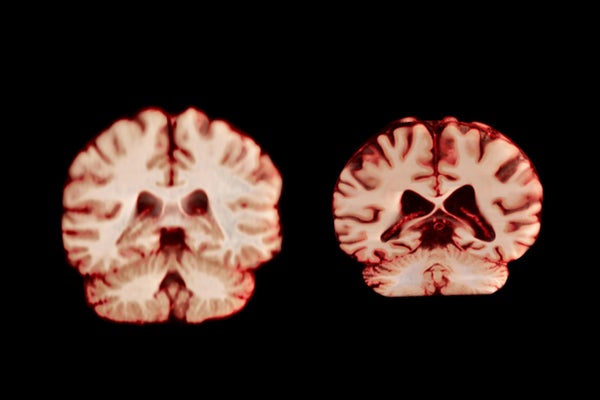

Visualization comparing a healthy brain and a brain affected by Alzheimer's disease

A healthy brain (left) and a brain affected by Alzheimer’s disease.

TheVisualMD/Science Source